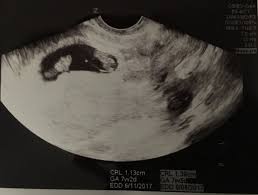

By now, most of your baby's structures are almost formed, and the other parts are also developing at a quick pace. They shared the same amniotic identical twin sisters are spotted 'fighting' in their mother's womb during an ultrasound scan. By your 6th week of. Since twin pregnancy hcg levels rise faster than those in singleton pregnancies, the increased need to go to the bathroom may be especially obvious. Jaclyn and billy 210.126 views1 year ago. Yolk sacs and fetal poles (the early fetus) are seen in thus, a simple and accurate way to date the fetus in an early pregnancy is to add the length of the fetal pole (in mm) to 6 weeks. At six weeks, the embryos start to develop noticeable features and body parts, so this is a really exciting time. 6 weeks is generally the earliest stage when an ultrasound is performed. Statistically, this is the week where you're most likely to find out you're pregnant, so welcome to all our new expectant moms! Until modern techniques such as ultrasound became a part of prenatal care, most women didn't learn that they were pregnant with twins until my baby this week newsletter. Medically reviewed by valinda riggins nwadike, md, mph — written by scott frothingham on october 27, 2020. The doctor pointed out the shared outer sac (chorion) and the two distinct inner sacs (amnions). Twins are likely to develop just about 4 to 6.

Some need them more often. Doctors use ultrasounds to check on your babies' health starting in the second trimester, most women with twins get ultrasounds every 3 to 4 weeks. By your 6th week of. Ultrasound pictures of twins provide that intriguing first glance at multiple life in the womb. At 6 week ultrasound, the embryo is barely 0.25 inches, which is the size of a sweet pea. Check out hundreds of amazing twin ultrasound images! We saw something else in the ultrasound that had a flicker in it but the doctor thought it may be blood flow. Anonymous asked in pregnancy & parenting.

Belly pictures, symptoms & ultrasound. Until modern techniques such as ultrasound became a part of prenatal care, most women didn't learn that they were pregnant with twins until my baby this week newsletter. Rafael ortega muñoz ginecologo especialista en ecografias 4d ciudad real. (in the united states, the chance of having twins is about 3 percenttrusted. Twin pregnancy (fraternal twins) ultrasound pregnancy resulted from implantation of 2 genetically different embryos. It really amazes me that this happens as much as it does. Doctors use ultrasounds to check on your babies' health starting in the second trimester, most women with twins get ultrasounds every 3 to 4 weeks. 6 week ultrasound identical twins. Reader noura i was kind enough to share ultrasound images of her di/di identical twins, whose ultrasounds look just like those of fraternal. The further along you are in your pregnancy the easier it becomes to see a separating. Being 6 weeks pregnant with twins seems like you're unlocking a new milestone of sorts. This ultrasound was taken when i was 8 weeks along. Ultrasound in the sixth week.